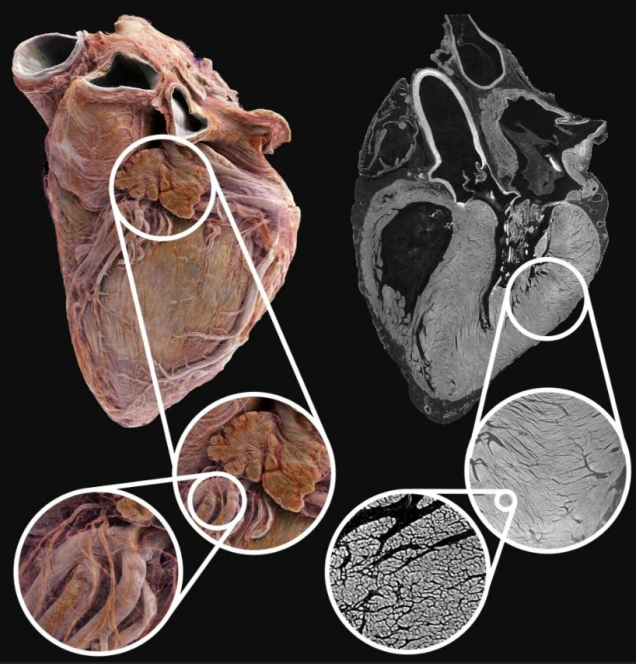

Bu teknoloji, kalbin tamamını gösterirken aynı zamanda çok küçük detaylara kadar yakınlaşma imkanı sunuyor.University College London'dan araştırmacılar, bu yeni yöntemle bir sağlıklı ve bir hasta kalbi incelediler. Kullandıkları teknik, Hiyerarşik Faz-Kontrast Tomografisi (HiP-CT) adı verilen özel bir X-ışını yöntemi, bu yöntemle kalbin yapısını insan saçının genişliğinin yarısı kadar küçük ölçekte (20 mikrometre) gösterebiliyor.

Bu teknolojinin en önemli özelliği, kalbi kesmeden tüm yapısını görebilmesi. Böylece doktorlar, kalp ritim bozuklukları gibi hastalıkların altında yatan nedenleri daha iyi anlayabilecek ve yeni tedavi yöntemleri geliştirebilecekler.Çalışma, dünyanın en güçlü X-ışını kaynağına sahip Avrupa Sinkrotron Radyasyon Tesisi'nde (ESRF) gerçekleştirildi. Yüksek radyasyon dozu nedeniyle bu yöntem şu an için sadece bağışlanmış kalplerde kullanılabiliyor.